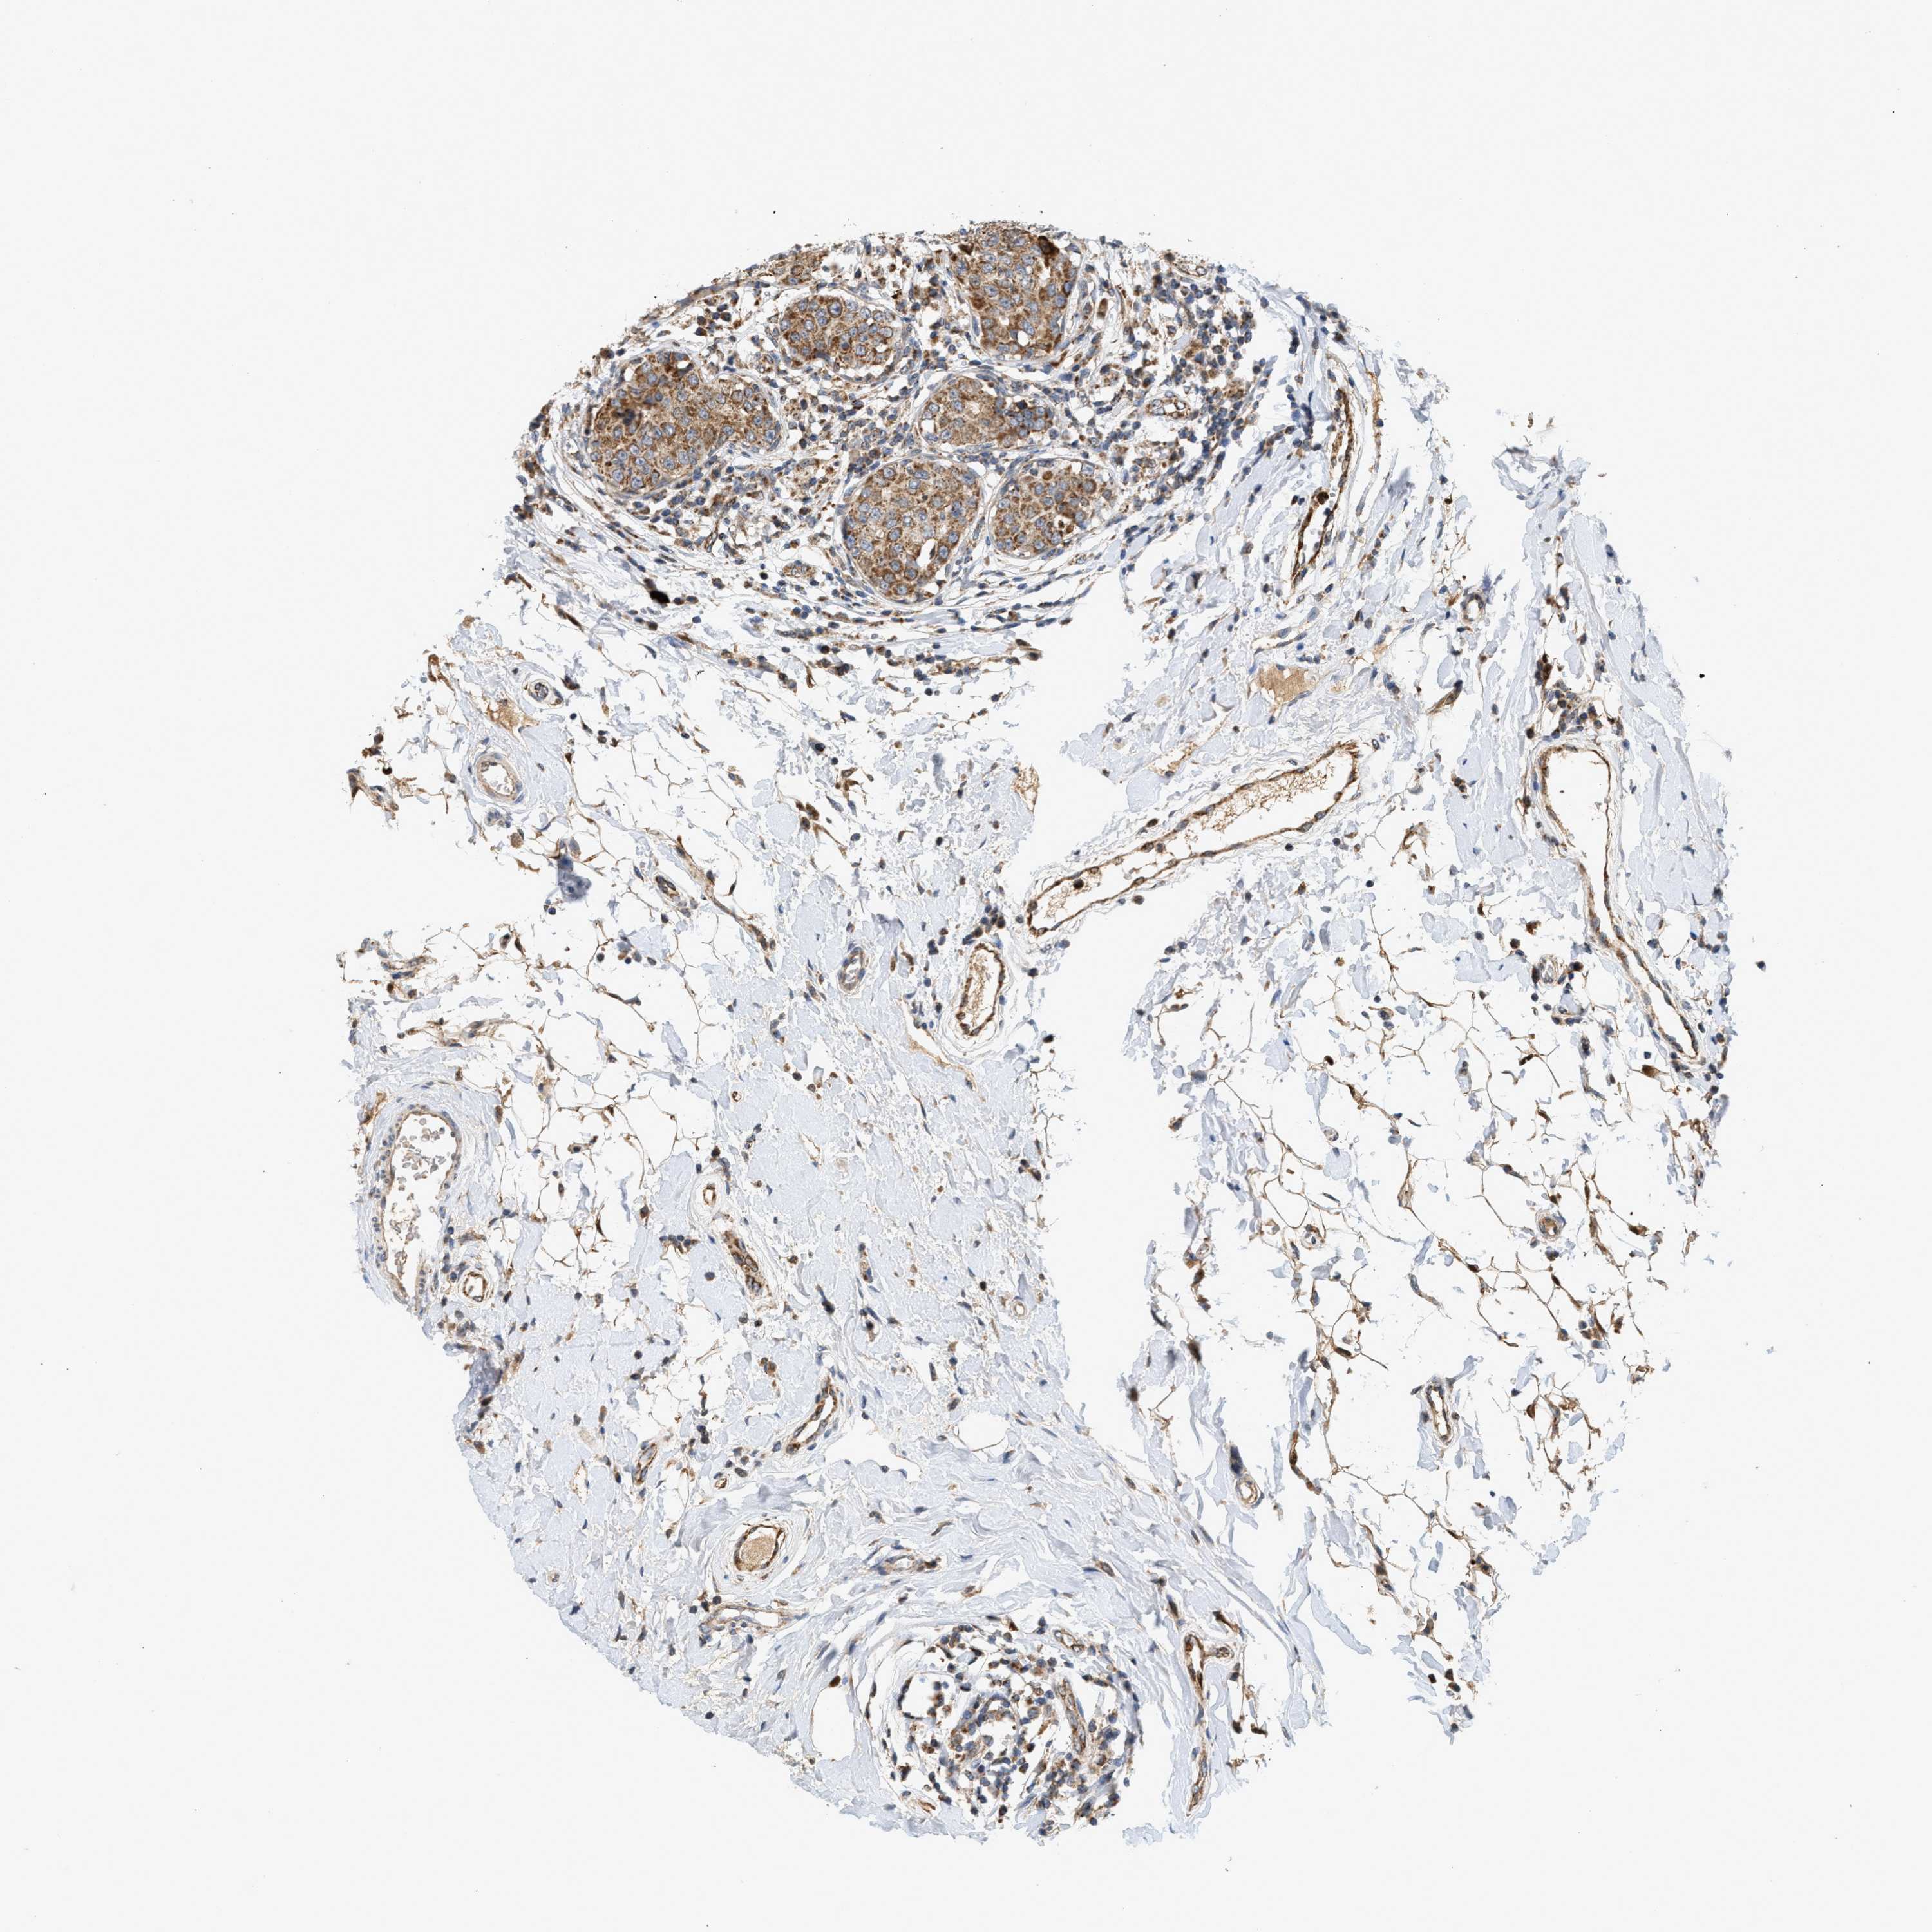

CANCER BREAST CANCER Show tissue menu

BRCA TCGA BRCA VALIDATION PROTEIN EXPRESSION